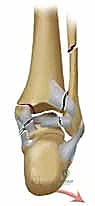

المرحلة الثالثة: رد العظام وتثبيت الكعب الوحشي (الشظية)

يبدأ الجراح عادة بإصلاح الشظية لأنها تعتبر "العمود الفقري" لاستقرار الكاحل. يتم إرجاع قطع العظم إلى مكانها التشريحي الطبيعي (الرد المفتوح). ثم يتم تثبيتها باستخدام شريحة معدنية (Plate) ومجموعة من المسامير (Screws) لتثبيتها بقوة.

المرحلة الرابعة: تثبيت الكعب الإنسي (الظنبوب)

بعد استقرار الجانب الخارجي، ينتقل الجراح للجانب الداخلي. يتم تنظيف منطقة الكسر من أي أنسجة محشورة، ثم يتم رد الكعب الإنسي وتثبيته غالباً باستخدام مسمارين طويلين (Cancellous screws) أو تقنية الأسلاك والشد (Tension band wiring) حسب شكل الكسر.

المرحلة الخامسة: التقييم الديناميكي وإغلاق الجرح

هنا تبرز خبرة أفضل طبيب عظام في صنعاء واليمن. يستخدم الدكتور هطيف جهاز الأشعة التلفزيونية داخل العمليات (C-arm) للتأكد من وضعية المسامير والشرائح. وفي حالات معينة، قد يستخدم المنظار المفصلي (Arthroscopy 4K) لفحص سطح الغضروف من الداخل والتأكد من خلوه من أي شظايا عظمية صغيرة.